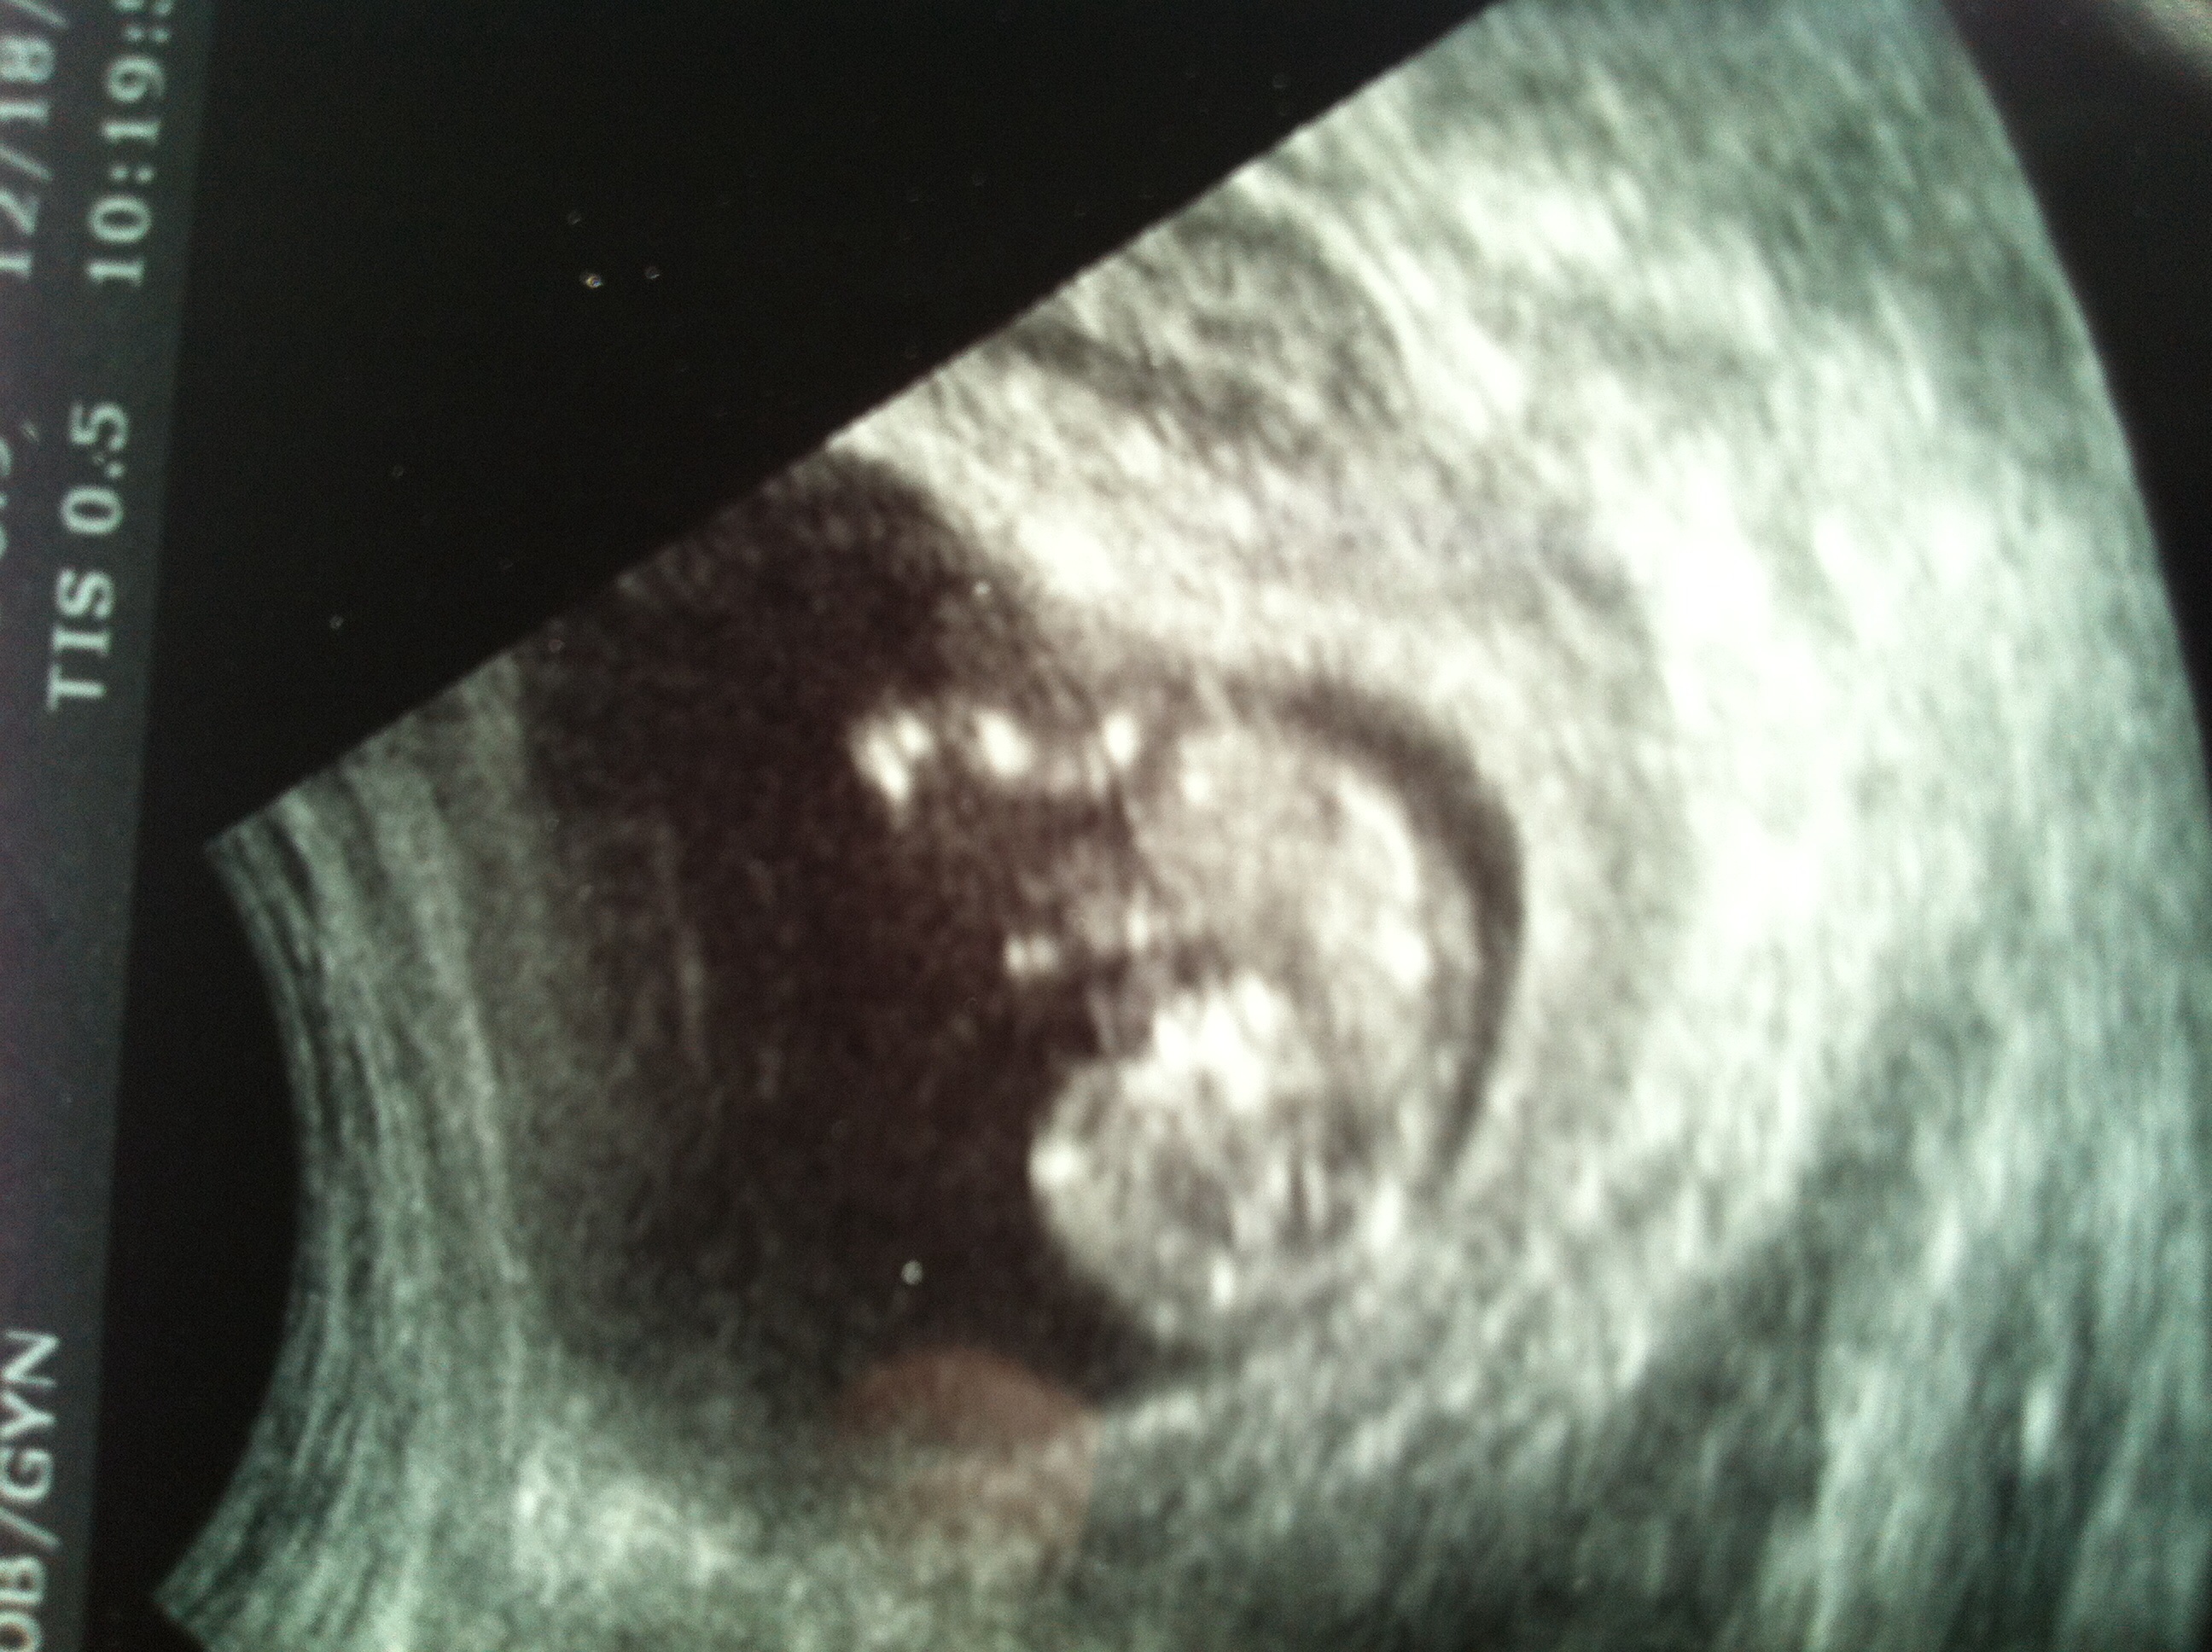

Let's see those blumps, ladies!